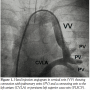

Under general anesthesia, venous access was achieved by both femoral veins; right femoral vein was selected for delivery of the device and left femoral vein to advance an angiographic Berman’s catheter to the left pulmonary artery. Angiogram of the VV was performed with a marked pigtail catheter and 10 mm was the maximal diameter measured. We selected a 14 mm device (Amplatzer Vascular Plug II, AGA Medical) and a Torq Vue 180° 7 Fr sheath for delivery (AGA Medical), which has a radio-opaque market at the tip and is primarily used

to deliver closure devices for patent ductus arteriosus. The design of this sheath with 180° curve was ideal to achieve the desired position. Through femoral vein approach, with a right coronary Judkins catheter and the aid of a 0.035″x 260 cm Wholey floppy wire (Mallinckrodt Inc.) we positioned the catheter in the VV and exchanged the guidewire for an extra stiff Amplatz (Cook Medical Inc.). The delivery sheath was advanced just above the pulmonary vein (Figure 1). Dilator and extra stiff wire were retrieved under sealed water to avoid air embolism considering that all this venous system was connected to the LA. The vascular plug was advanced until the tip of the sheath. Deployment of the device was performed by retracting the sheath over the delivery wire. Levophase angiogram in the left pulmonary artery was recorded to reveal the exact position and permeability of the pulmonary veins. VV was completely occluded, and pulmonary venous blood flow was directed towards LA (Figure 2). With the device still attached, an angiogram through the delivery sheath was performed to rule out obstruction of the IV (Figure 3). After release, manual contrast injection through a venous access of the left superior limb showed no obstruction of the systemic venous flow (Figure 4). Patient was discharged from the hospital without events 24 H after intervention and antiplatelet therapy with aspirin was indicated for 6 months.